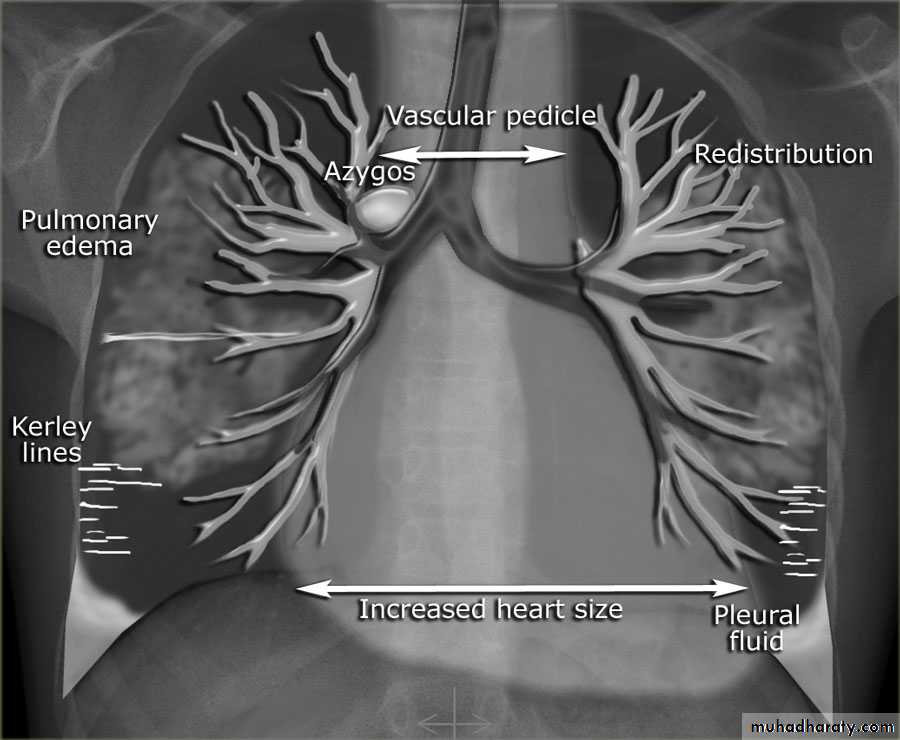

With left sided congestive cardiac failure, the features are that of pulmonary edema which includes:

central pulmonary venous congestion ( prominent hilum )

cephalization of pulmonary veins ( upper lobe pulmonary venous diversion )

pulmonary interstitial edema

pulmonary alveolar edema

Cardiomegaly

Pleural effusion

Septal lines, also known as Kerley lines, are seen when the interlobular septa in the pulmonary interstitium become prominent. This may be because of lymphatic engorgement or edema of the connective tissues of the interlobular septa. They usually occur when pulmonary capillary wedge pressures reach 20-25 mmHg ,

Kerley A linesThese are 2-6 cm long oblique lines that are <1 mm thick and course towards the hila. They represent thickening of the interlobular septa

Kerley B lines

These are 1-2 cm thin lines in the peripheries of the lung. They are perpendicular to and extend out to the pleural surface . They represent thickened sub pleural interlobular septa and are usually seen at the lung bases.Interstitial pulmonary edema

radiograph include if pressure > 25 mmHg the findings of :

cardiac size/cardio-thoracic ratio: useful for assessing for an underlying cardiogenic cause or associationbat wing pulmonary opacities

presence of peri-bronchial cuffing

septal lines: Kerley lines become more prominent

pleural effusions

pulmonary venous engorgement/pulmonary blood flow distribution upper lobe pulmonary venous diversion

Pulmonary venous hypertension

Pulmonary venous hypertension (PVH) results from an increase in pressure in the pulmonary veins, usually as a result of left atrial hypertension. This is measured clinically as an increase in the pulmonary capillary wedge pressure (PCWP) over the normal 12 to 14 mmHg.Mild elevation of the PCWP results in redistribution of the pulmonary blood flow to the non-dependent lung zones

As the pressure approaches 20 mmHg, interstitial edema develops